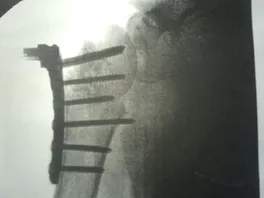

ich hatte am freitag den 11.05.12 einen unfall mit meiner hp4 und habe richtig heftig aua bekommen. ich habe einen 4 fachen schulterbruch,rippenprellungen und eine übberdähnung des kreuzband am rechten fuss erlitten. schürfwunden sind auch genug vorhanden. ich wurde am tag drauf an der schulter operiert und habe jetzt eine titanplatte mit 7 schrauben drin.

hier mal paar bilder.